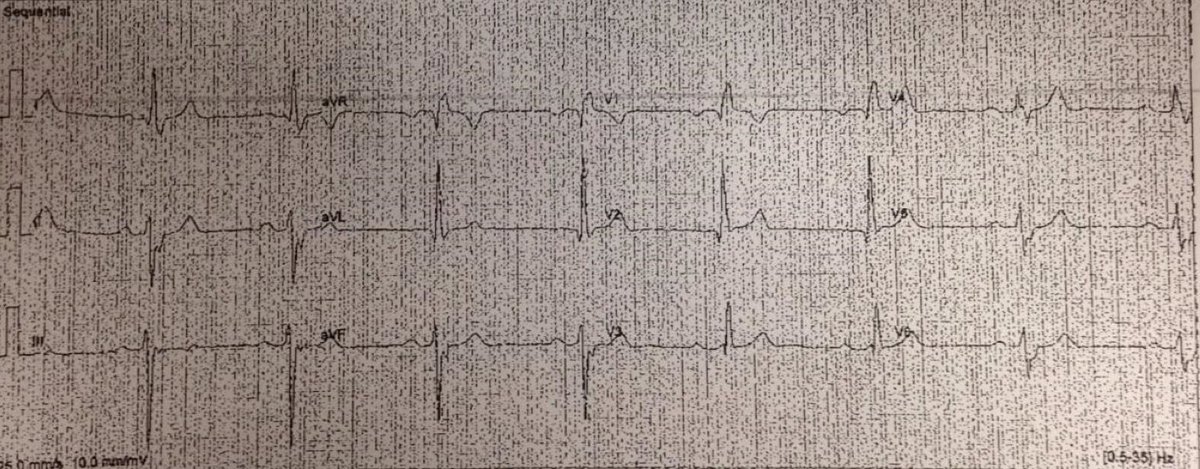

What’s the rhythm? First portion just looks like PACs in a pattern of bigeminy hitting a partially refractory AV node with resulting long PR. But why do the PAC PR intervals suddenly shorten at the end?@DidlakeDW @ecgrhythms @The_Nanashi_O #ECG #CardioTwitter